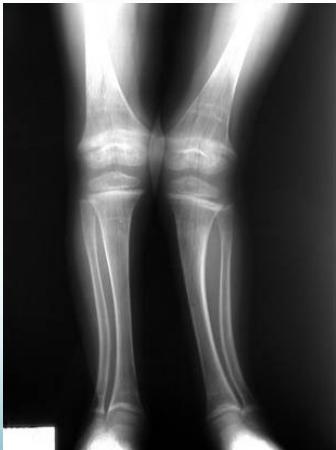

Radiological Assessment

Indications: X-ray when severe or possibly pathologic

Recommended Views:

- Standing AP film: Long film (hips to ankles) with patellae directed forwards

Radiological Parameters to Assess:

- Medial Physeal Slope

- Femoral-Tibial Axis